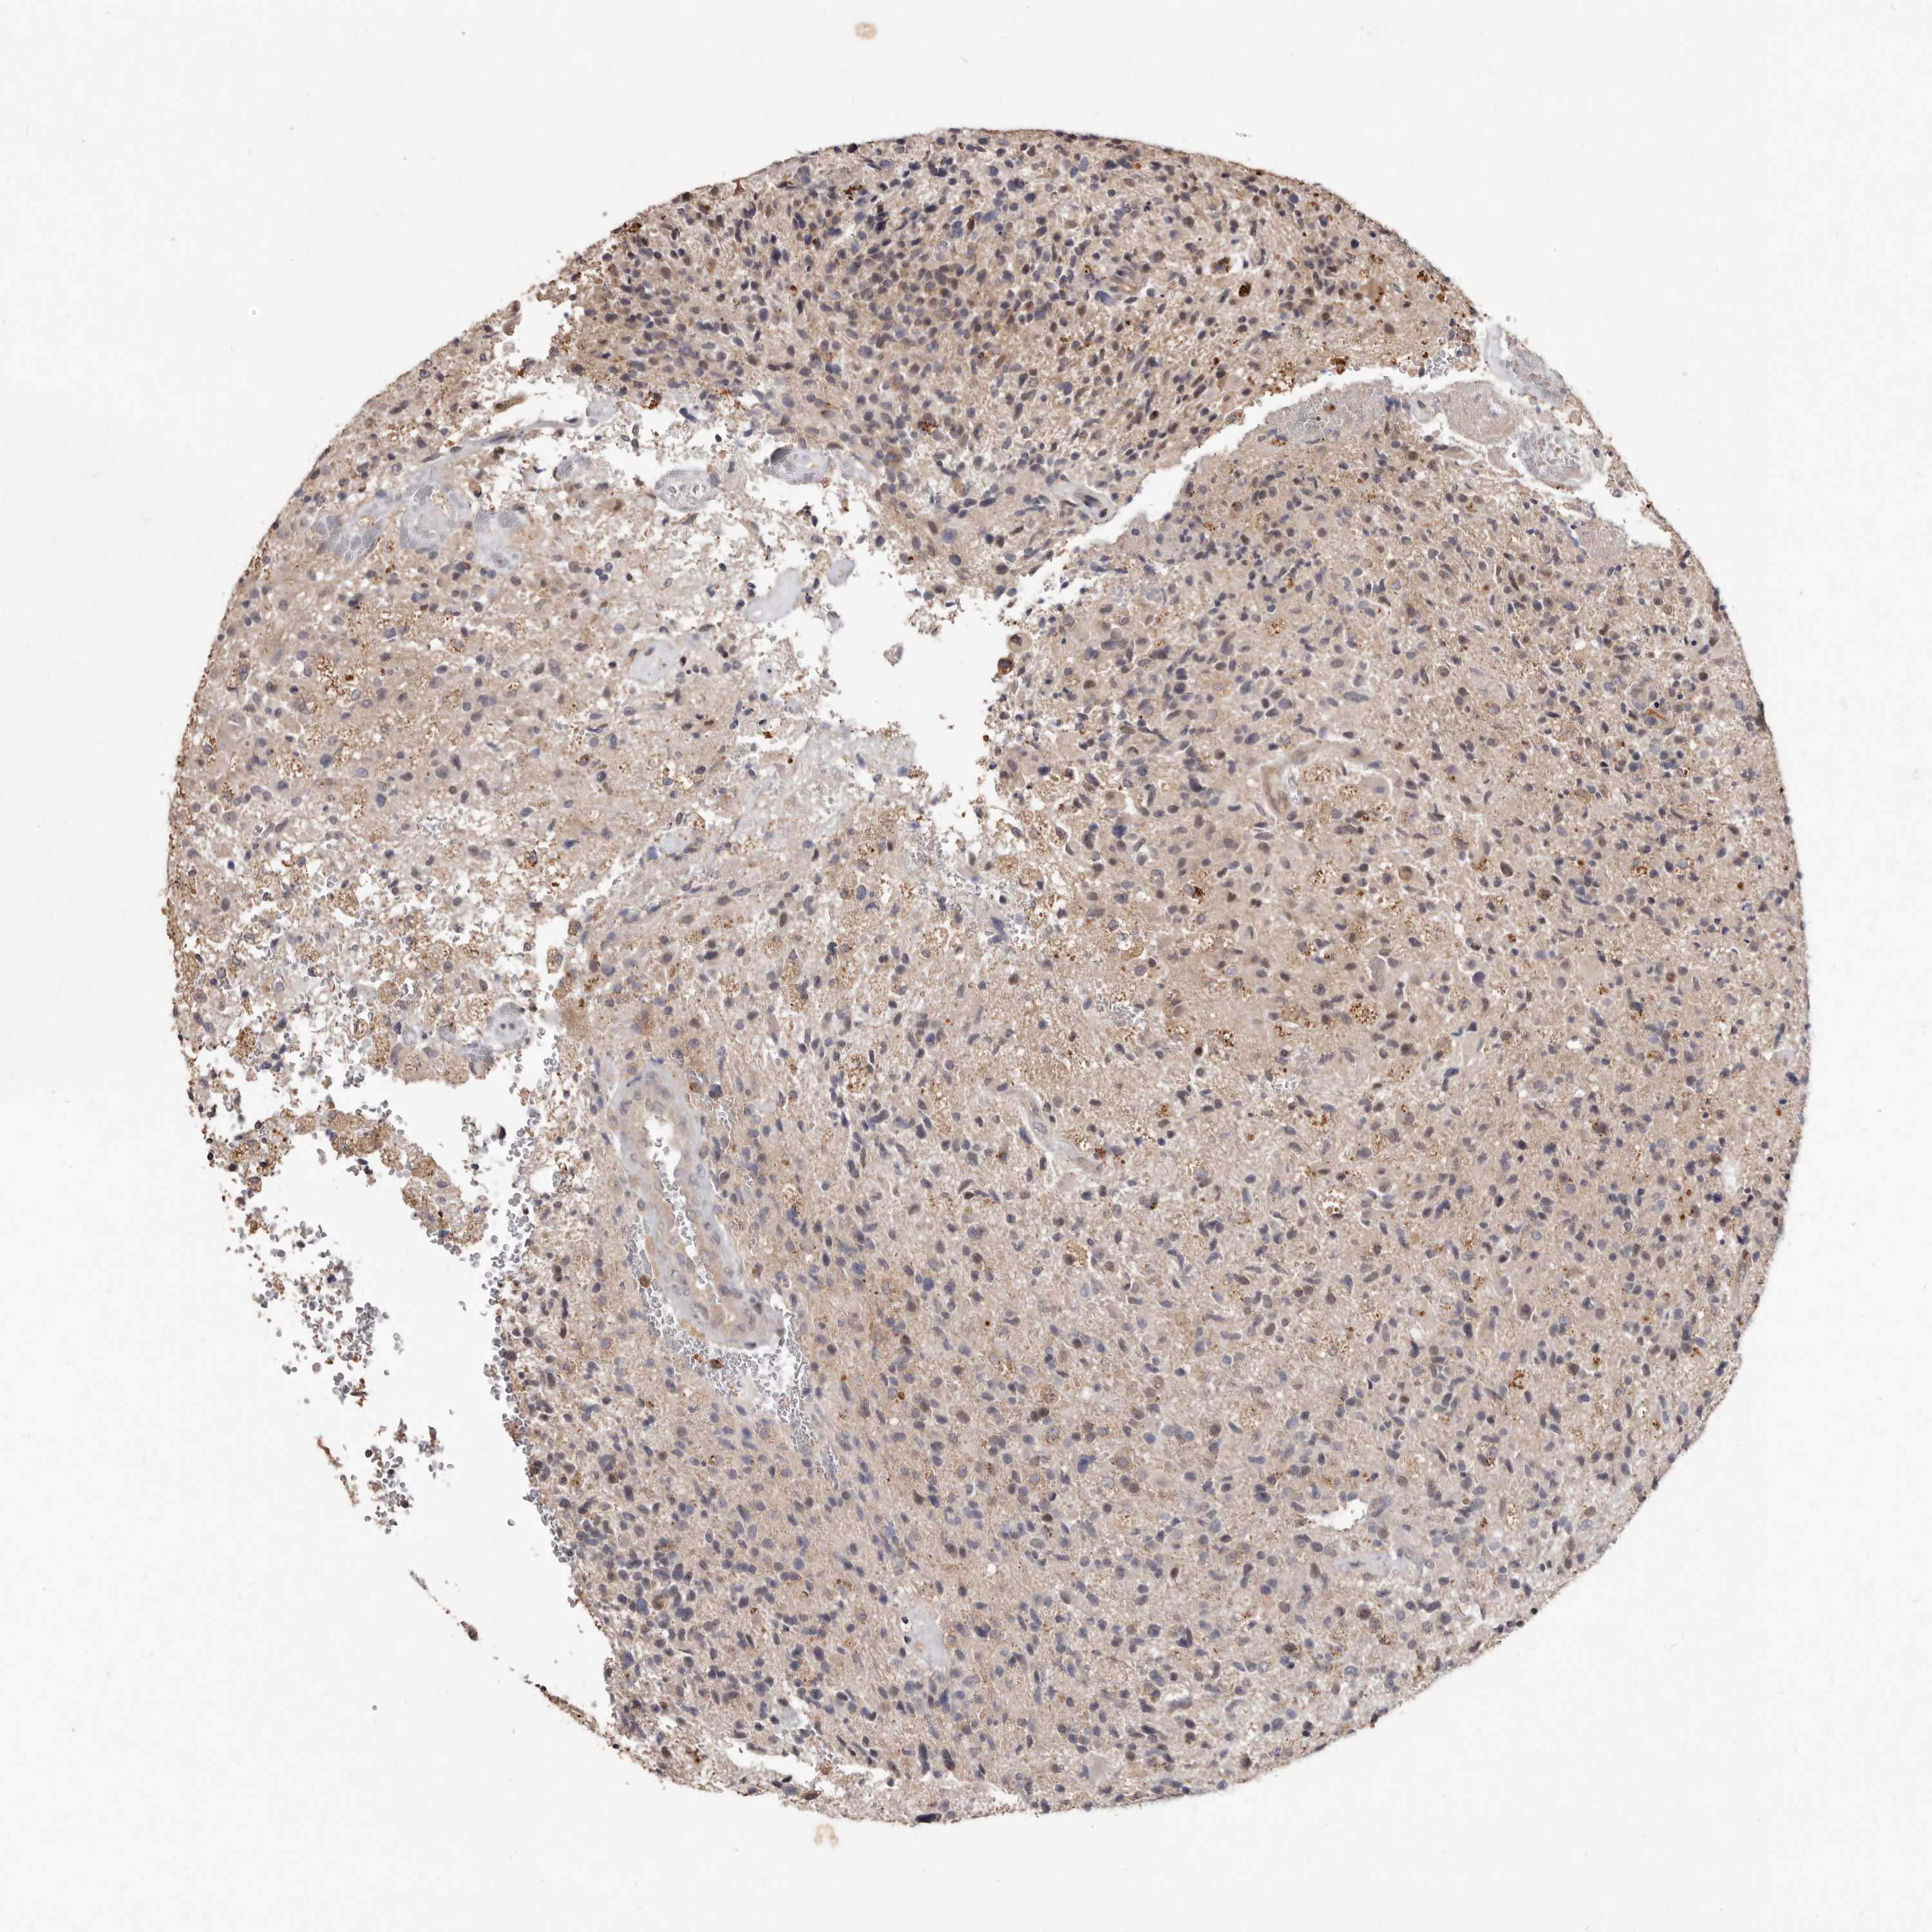

GLIOMA - Protein expressioni

A mouse-over function shows sample information and annotation data. Click on an image to view it in a full screen mode. Samples can be filtered based on level of antibody staining by selecting one or several of the following categories: high, medium, low and not detected. The assay and annotation is described here.

Note that samples used for immunohistochemistry by the Human Protein Atlas do not correspond to samples in the TCGA dataset.

Antibody stainingi

Antibody staining in the annotated cell types in the current human tissue is reported as not detected, low, medium, or high, based on conventional immunohistochemistry profiling in selected tissues. This score is based on the combination of the staining intensity and fraction of stained cells.

Each image is clickable and will lead to virtual microscopy that enables deeper exploration of all samples and also displays staining intensity scores, fraction scores and subcellular localization as well as patient and tissue information for each sample.

HPA022434

HPA022953

HPA022959

HPA028758

CAB007783

Glioma, malignant, High grade

Glioma, malignant, Low grade

Glioblastoma, NOS